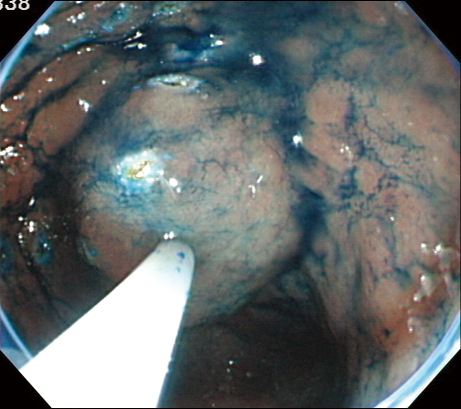

It facilitates incision and dissection in total while maintaining the advantages of the conventional ITknife. The incision and dissection speeds have also been increased even more.

However, you have to keep in mind that ITknife2 is quite a bit sharper. If you make the same kind of strokes you’re used to with ITknife, you may cut too deeply and increase the risk of perforation. You should be careful with the knife until you get used to it. It’s also a good idea to use the EndoCut mode. Or step on the high-frequency switch intermittently with a continuous wave mode, to prevent ITknife2 from slipping and causing a perforation. In addition, as with ITknife, laying the knife down too much increases the risk of perforation, so ITknife2’s sheath should be held slightly to upright direction than ITknife. Remember to be careful to avoid problems in the initial introductory phase. However, you won’t need to think about these points once you’ve gotten used to ITknife2 after several uses.

In such a case, point the insulated tip straight toward the muscle layer and swing laterally by manipulating the endoscope or using the angulation function to cut the site little by little.

I have rarely needed to use a needle knife. However, a needle knife offers better cutting performance when an ulcer scar is very hard. In such a case, I use a needle knife until the mucosa is curled up in a certain amount and then I switch to ITknife2.